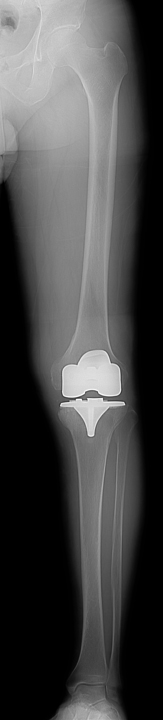

人工膝関節置換術

人工膝関節置換術とは、傷んで変形した関節を人工の関節に置き換える手術です。人工関節の表面は滑らかで神経もないため、この手術を受けることによって、関節は滑らかに動くようになり、痛みもほとんど感じなくなります。また、O脚やX脚に変形した膝が、手術によって真っすぐな膝になります。痛みなく歩けるようになると、日常生活を送りやすくなり、生活の質(QOL)を改善することができます。

手術では、まず変形して傷んだ大腿骨と脛骨の表面の骨を切除します。大腿骨側と脛骨側の骨にそれぞれ金属製の人工関節(大腿骨・脛骨コンポーネント)を固定します。脛骨コンポーネントの上面に超高分子量ポリエチレン製の人工の軟骨(インサート)を設置します。人工膝関節は大腿骨コンポーネントとインサートの間で滑らかに動く構造になっています。

![]() 術後レントゲン |